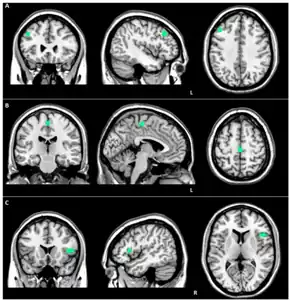

| Brain MRI of a female of 65 years with frontotemporal dementia. Cortical and white matter atrophy of the frontal lobes is clear in all images. | |